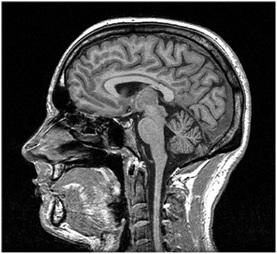

MRI stands for Magnetic Resonance Imaging. This technology relies on magnetism. It’s a more recent advancement compared to CT scans. MRI uses magnetism to create a 3D image of the body’s interior.

Similar to CT scanners, MRI machines have a moving platform. Patients lie down on this platform and are moved into a narrow cylinder. Magnets within the cylinder generate a strong magnetic field around the patient’s body. The cylinder is somewhat narrower compared to CT scanners. It’s crucial to remove all metallic objects from the body before an MRI scan. MRI scans can take around 30 minutes to complete.

Key components of an MRI scanner include: